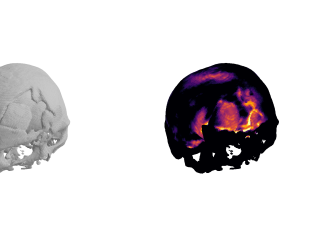

We show some slices with examples of ICH in \figurereffig:qualitative_ich as well as surface renderings of scans of subjects with cranial fractures in \figurereffig:qualitative_fractures. (As a reference we also included the same examples for the AE in Appendix D in \figurereffig:qualitative_ich_ae.) It is noticeable that the reconstruction error is high where there is an anomaly. The reconstruction error generally seems to continuously depend on the amount of the patch that is anomalous, as the error maps generally seem to be rather smooth.

The performance for the models used for \figurereffig:qualitative_ich and LABEL:fig:qualitative_fractures are shown in \figurereffig:roc_performance. We observe see that the detection of fractures is the more challenging task for our method than the detection of ICH. This might be due to the smaller number of scans available to evaluate it on (see Appendix B). To put these results in context we provided a table with the inter rater agreement on these tasks in Appendix B: The performance in terms of AUROC is around lower than the average raters.

fig:qualitative_fractures